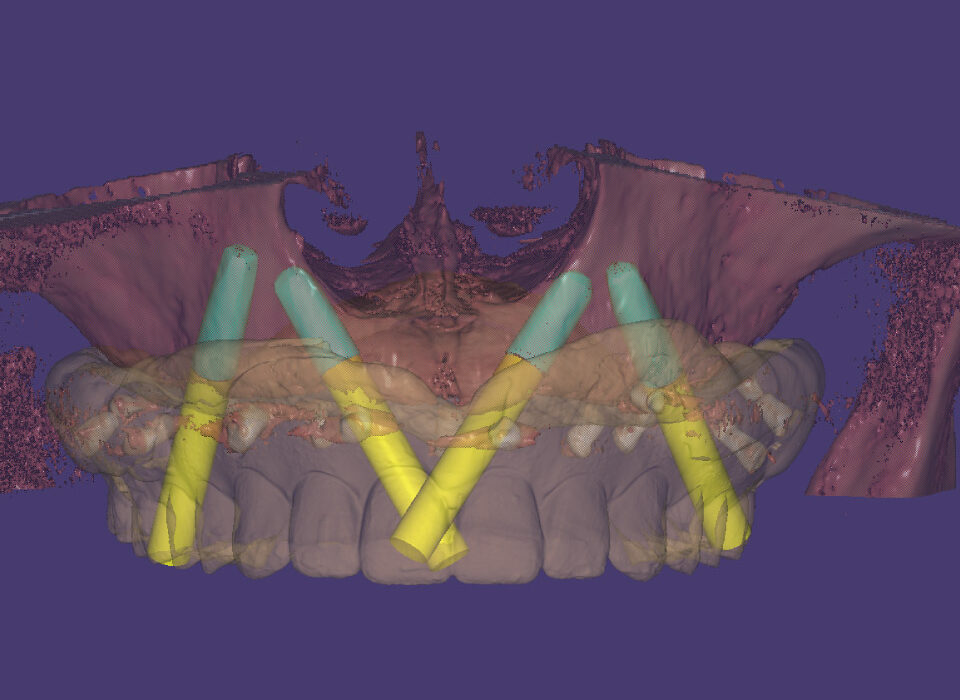

Surgical Guides

Surgical Guide is a digital tool that ensures accurate positioning and angulation of implants, which is crucial for the success and longevity of the implant. We fabricate different types of surgical guides, including tooth-borne, mucosa-borne, and bone-borne guides i.e stackable.